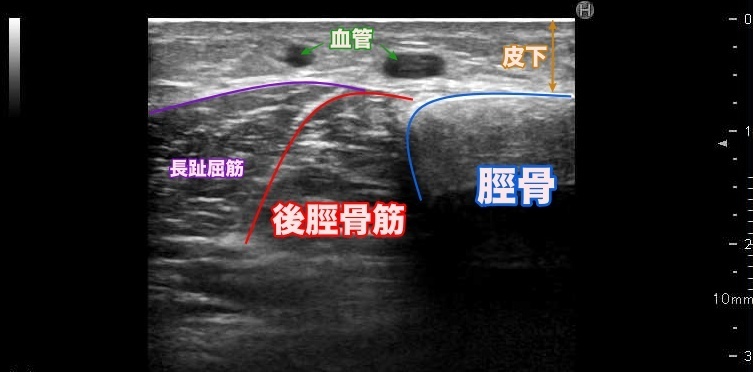

超音波では、脛骨周囲の骨膜が腫れているかを確認する事が出来ます。

骨膜が腫れている場合、症状が経過によっては疲労骨折の可能性も考えられます。

【下腿を上から輪切りにして見た場合】

痛みは脛骨(スネ)に沿ってうずくような鈍痛で始まります。ある一点に集中する痛み(この場合は疲労骨折の可能性も)とは違い、 筋肉が骨に付着するラインに沿って起こります。主な足関節底屈筋(下腿三頭筋、ヒラメ筋、後脛骨筋、長趾屈筋、長母趾屈筋)は、脛骨に付着しています。

足関節底屈筋(下腿三頭筋、ヒラメ筋、後脛骨筋、長趾屈筋、長母趾屈筋)は、脛骨の内側後面に付着しています。

US(超音波検査)